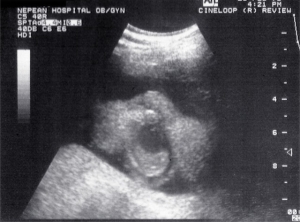

- Obstetrics 1973

Scans – Obstetric and General